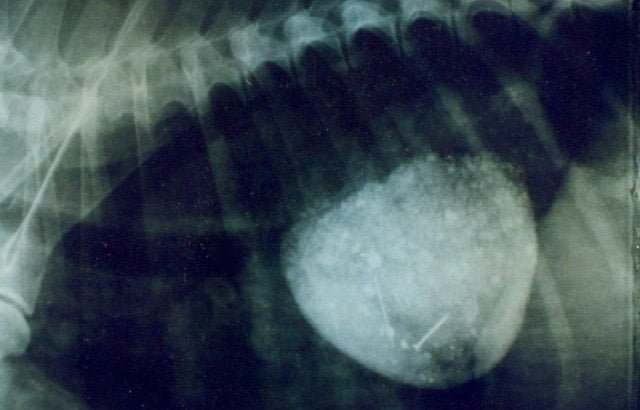

Veterinary Surgery and RadiologySurgical affection of liver in animals are portosystemic shunts, tumors, abscess, trauma, Cholelithiasis etc.

Surgical affection of liver in animals are portosystemic shunts, tumors, abscess, trauma, Cholelithiasis etc.